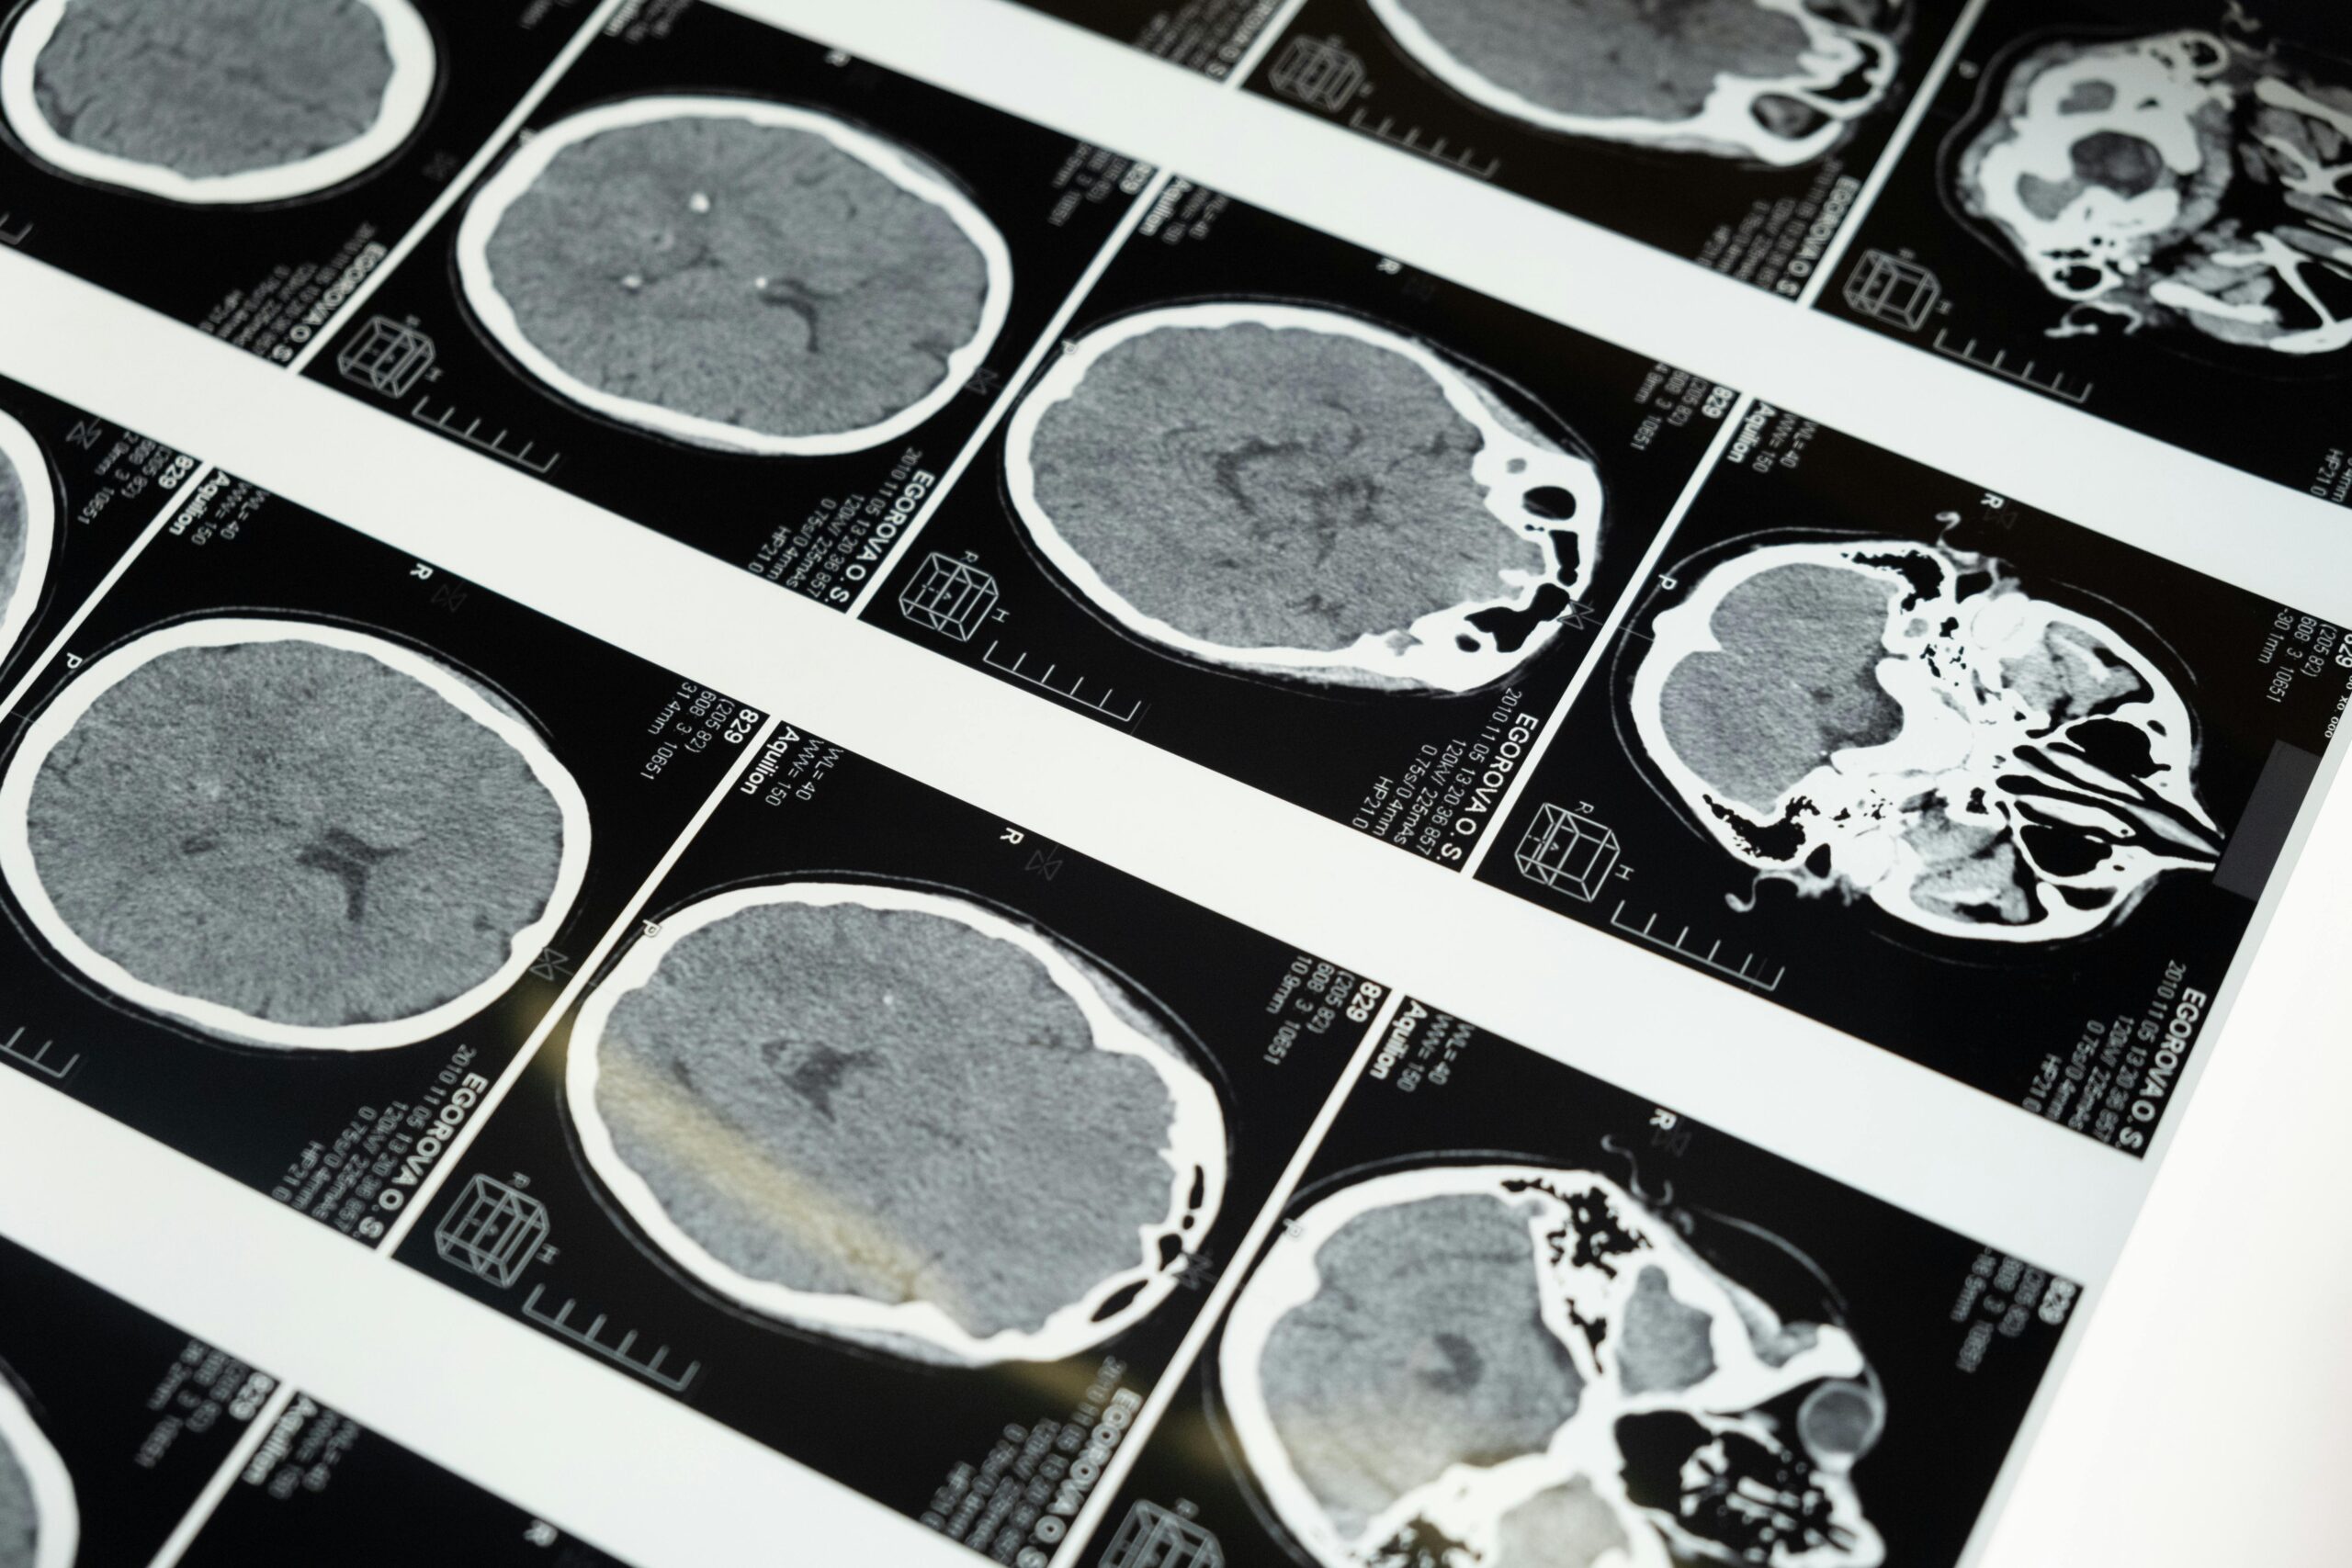

A growing body of work indicates there are detectable differences in brain development among many autistic individuals, differences that tend to emerge earlier rather than later in life and may set developmental trajectories before behavior becomes fully evident.

Neuroimaging and longitudinal investigations have highlighted patterns of connectivity and growth that distinguish autistic brains from neurotypical ones, suggesting that biology and experience interact to shape how social communication and repetitive behaviors arise.